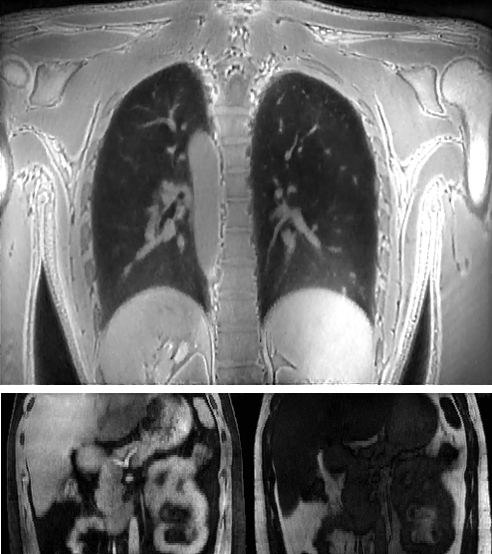

Medical imaging is now used extensively for accurate diagnosis, real-time intervention, and precision medicine. Our work has been focused on fast, high-resolution imaging augmented with functional and metabolic mapping. For example, dynamic 4D MRI under free breathing has been developed using PNCRNNs, with the reconstruction time as fast as 50 bin per second, offering substantial improvement of the image quality for dynamic golden-angle radial imaging of the abdomen. Novel imaging techniques have been developed for high-resolution whole-brain neurometabolic mapping, shedding light on in vivo molecular biomarkers for various brain diseases including stroke, brain tumor, and neurodegenerative disorders. A model-based deep learning architecture, referred to as MoDL-QSM, was developed with improved accuracy for quantifying tissue susceptibility for precise electrode implantation for deep-brain stimulation. To meet the demands for automated identification and localization of the vertebrae, pancreas, colon, lung nodules and other organs in low-dose CT, algorithms integrating local image details and global image patterns have been proposed. To extend the clinical use of nonlinear regression in medical imaging and image analysis, a deep negative correlation learning framework has been proposed to yield a deep regression of ensemble where each base model is both accurate and generalisable.

Dynamic 4D MRI of the abdomen

1. Zhang Y, She H, and Du YP. Dynamic MRI of the

abdomen using parallel non-cartesian convolutional recurrent neural networks.

Magnetic Resonance in Medicine, 2021, 86:964-973.